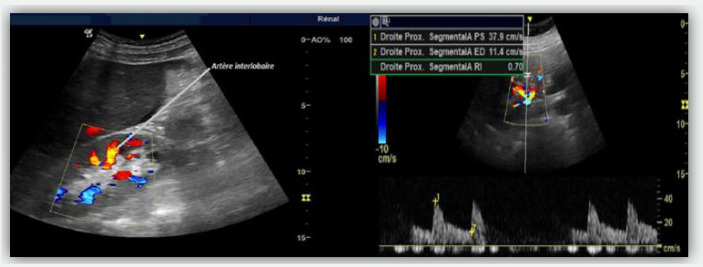

Introduction: Acute kidney Injury (AKI) is the most frequent complication of septic shock. Bedside ultrasound measurement of the renal resistance index (RRI) is an interesting way of assessment of renal hemodynamics.

Methods: This is a prospective observational study including patients in septic shock and on mechanical ventilation. Data collection was carried out between October 2022 and July 2023. RRI was measured during the first five days of shock.

Results: Forty patients were enrolled in the study. Mean age was equal to 51 years ±13.4 and sex ratio was equal to 2.33. The mean RRI value was 0.704, with extremes ranging from 0.52 to 0.83. Patients were divided into two groups : AKI(+) and AKI (-). RRI in the group AKI (+) was higher than in the group AKI (-) (0.757 vs. 0.672; p=0.013). RRI predicted the occurrence of AKI, with an area under the ROC curve of 0.75 (p=0.007) and a cut-off value of 0.71 (specificity=64%, sensitivity=73%).

Conclusion: Assessment of RRI could be a useful technique of predicting the onset of AKI in association with the conventional markers. Its validation will guide management towards optimal renal protection in patients with septic shock.